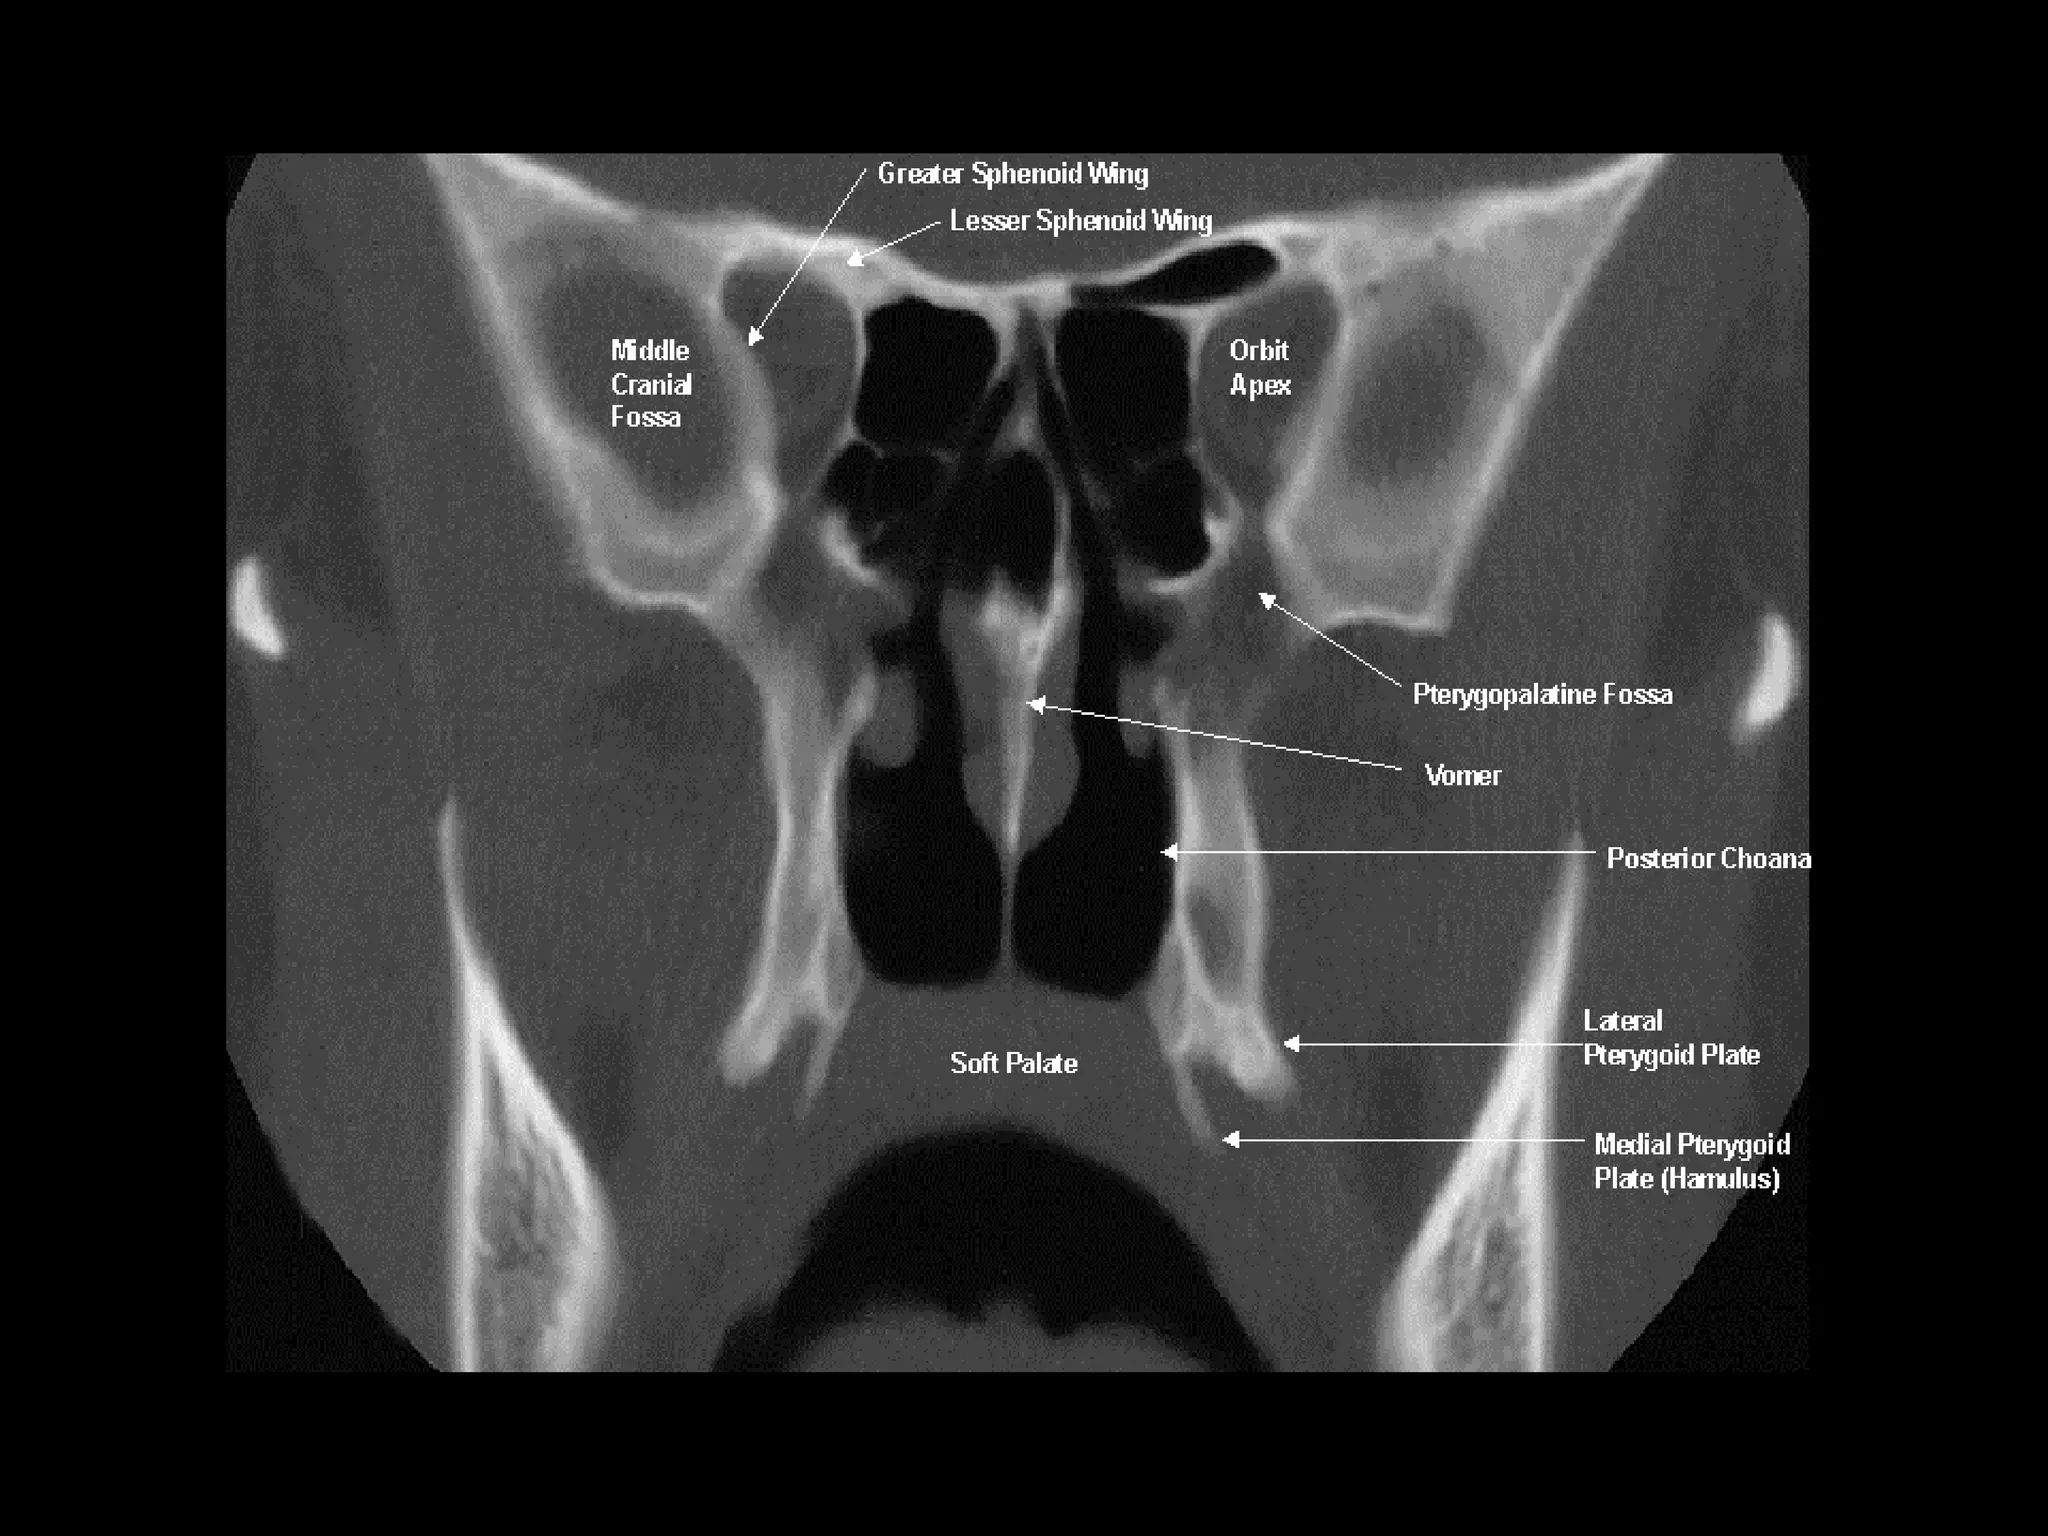

Radiographers are medical professionals who perform diagnostic imaging examinations and procedures to help physicians diagnose and treat diseases. They work under the supervision of radiologists to operate X-ray, CT, MRI, ultrasound and other medical imaging equipment and must have a strong understanding of human anatomy and pathology. Radiographers are responsible for correctly positioning patients, ensuring proper imaging techniques are used, and evaluating the quality of the resulting images.